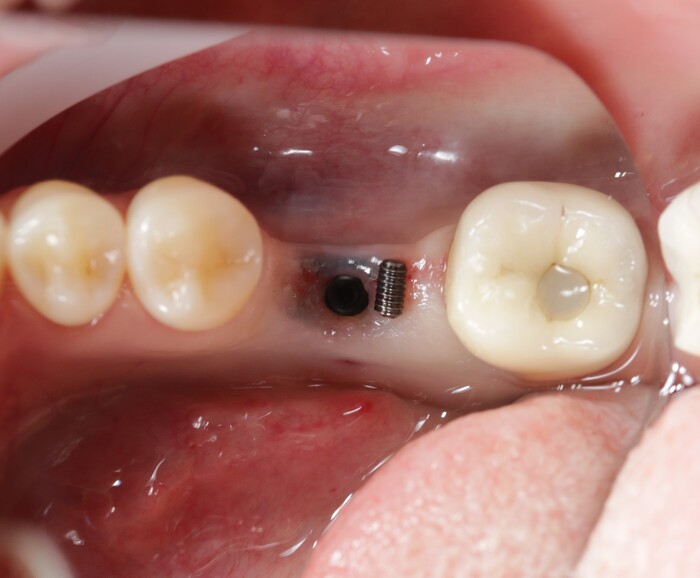

В январе 2018 молодой девушке была проведена имлантация в области 6го зуба на нижней челюсти слева, а коронка установлена в другом месте.

Ко мне же она пришла уже на профосмотр через месяц.

Ниже фрагмент компьютерной томографии, а интересующий имплантат справа снизу:

Увы, но рядом стоящий 7й зуб треснул пополам и было принято решение о его удалении и установке имплантата.

Для полной интеграции имплантата необходимо около 4х месяцев, но девушка пришла спустя 6, в июне 2018:

Жалоб нет, имплантат интегрирован. Следующим этом было снятие слепков и изготовление коронки. Ниже снимок от августа 2018:

Казалось, что все в порядке. Так, собственно, оно и было. Контрольный снимок в декабре 2019:

Проходит еще полтора года и пациентка вдруг приходит на осмотр с жалобами на подвижность коронки в области той самой 6ки, с которой мы начали. Сначала показалось, что просто раскрутился винт, фиксирующий коронку к имплантату.

И тут начинается самое интересное. Что такое абатмент мы выяснили из картинки выше, это переходный элемент между коронкой и имлпантатом. Так вот по всем технологиям и нормам он должен быть титановым. Как контрастирует титан на рентгеновском снимке вы можете заметить, посмотрев на имплантат. Видите разницу между 6м и 7м имплантатом?